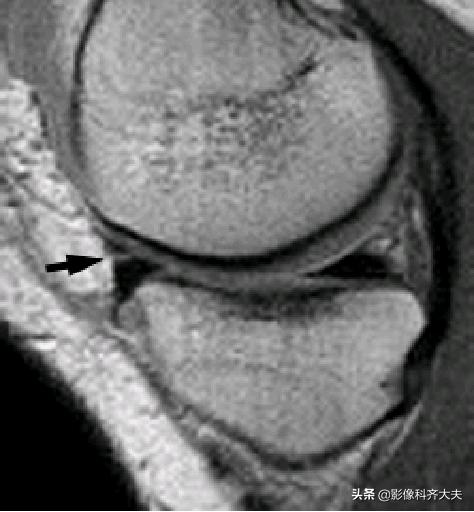

腘肌腱腱鞘: